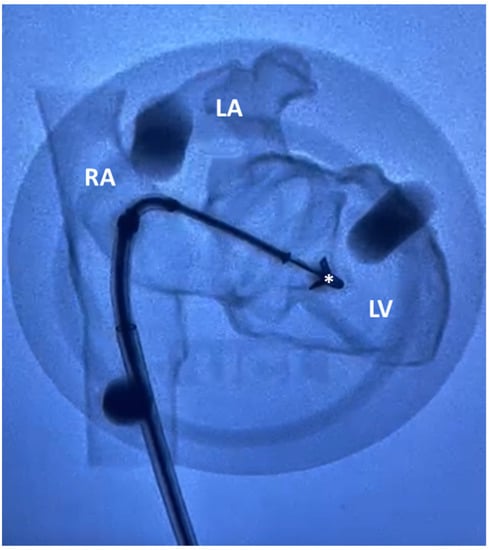

- Guide positioning in the LA and introducing CDS. The steerable guide catheter was advanced through the IVC, then transseptal crossing passage and insertion of CDS through SGC. A series of steering manoeuvres with the SGC and CDS were made to optimise the trajectory and orientation of the clip arms perpendicular to the line of coaptation, under direct visual access through the openings of the model.

- Advancing into LV through the MV while avoiding interaction with subvalvular apparatus and leaflet grasping. Once in place, MV leaflets were grasped by lowering the grippers and closing clip arms. Qualitative and visual assessments of MR were performed, possibly accompanied by leaflets regrasping, to reach optimal positioning and sufficient grasping.